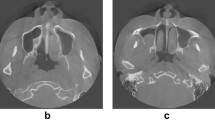

In order to minimize the potential influence of metal-related artifacts on the segmentation task, one of our exclusion criteria was patients with heavy metallic dental burden (MDB) including metallic dental implants, braces and crowns. CBCTs with heavy MDB due to metallic dental devices were automatically identified according to the following steps and excluded. First, two thresholds were empirically set with the first threshold (TH1) of 3070 HU and the second threshold (TH2) of 2500 HU, representing the density of metallic materials and the density of enamel, respectively. Second, MDB ratio (MDBR) was defined via dividing TH1 by TH2. Third, a third threshold (TH3) was set with the MDBR = 0.4. Fourth, heavy MDB was defined by MDBR > TH3. Fifth, patients with heavy MBD were excluded. A total of 24 patients were randomly selected from the rest of patients for segmentation of teeth in this study to prevent huge loading of manpower in defining the ground truth (GT). Patients were classified into 4 subsets, in which each subset containing same number of patients (N = 6) with the GT defined by different observers.